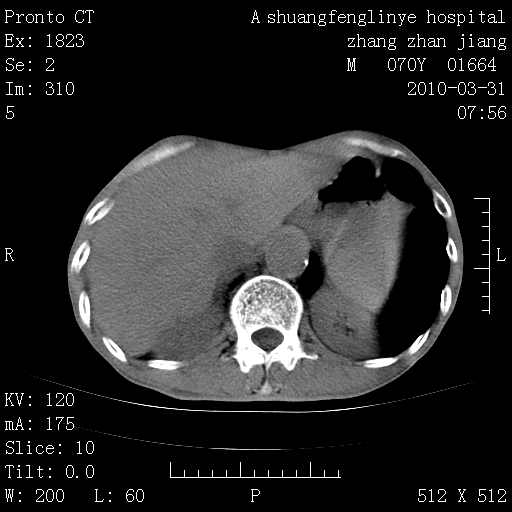

双上肺继发型tb并左上空洞形成,主动脉冠脉钙化。

1)两肺上叶继发性肺结核并左肺上叶空洞形成。2)冠状动脉及主动脉钙化。